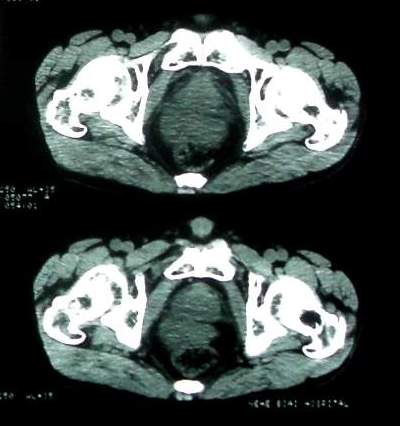

男 60岁,下腹部肿块半年余

前列腺肥大,密度不均。伴盆腔实性肿块。考虑前列腺癌伴盆腔转移。建议增强扫描。

考虑来源于肠道的肿瘤,乙状结肠?询问排便情况

盆腔恶性占位,间质瘤可能性大

乙状结肠间质瘤

盆腔恶性占位,间质瘤可能性大。

病理结果:肠系膜肉瘤

肠系膜的原发性肠系膜肿瘤比较少见,大体可分为囊性和实性两类。囊性肿瘤多为良性。实性肿瘤可以为良性和恶性,恶性肿瘤以恶性淋巴瘤为最多,其次是脂肪肉瘤、平滑肌肉瘤、纤维肉瘤等。恶性肿瘤约占实体肿瘤的6% [1] 。文献资料显示原发性肠系膜肿瘤约7%位于小肠系膜,其中60%位于回肠系膜和肠系膜根部,结肠系膜和阑尾系膜仅占20%左右 [2] 。由于肠系膜肿瘤在临床上不多见,症状无特异性,起病隐匿,早期可无症状,只有当肿瘤增大压迫周围的组织脏器时,才有可能出现相应的症状,并且这些症状常与邻近器官受压有关。腹部包块是主要的症状,临床表现为发热、乏力、腹部隐痛不适和饱胀感、消瘦,偶有呕吐及便秘,当肿瘤出血和囊肿突然增大时,可有腹痛,压迫症状有肠梗阻,下肢肿胀,肾盂积水等表现。体格检查时可触及腹部肿块,且活动度好,尤其是横向移动。b超可早期发现腹块,并可确定大小、性质及部位。x线钡剂灌肠检查,虽然不能提供系膜肿瘤的直接诊断依据,可显示为与肠管关系密切之外在性肿物,并可排除肠管、泌尿系等疾病[3] 。腹腔镜对原因不明的腹痛及性质不明的腹块,既可定性又可定位,其正确诊断率为74% [4] 。肠系膜良性肿瘤和恶性肿瘤的病程长短进行比较,恶性肿瘤绝大多数病程均在半年以内,没有超过2年以上。良性肿瘤大多数病程均在2年以上。这一点在诊断上具有鉴别意义。

病灶形态不规则,偏心性裂隙样坏死,支持恶性病变。来源不好定。感谢反馈结果--肠系膜肉瘤。